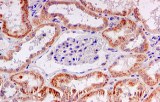

Microscope slides are categorized according to surface treatment to optimize performance across different applications. Plain slides are suitable for basic bright-field microscopy, while frosted-end slides facilitate precise and durable labeling. Charged or poly-L-lysine (PLL) coated slides enhance electrostatic adhesion of tissue sections, preventing tissue loss during staining—particularly important for immunohistochemistry (IHC) and in situ hybridization (ISH). Adhesive slides with silane or aminoalkoxysilane coatings are ideal for cytology smears and frozen sections, providing strong adhesion during high-temperature antigen retrieval.

- Charged or PLL-coated slides:

- strengthen electrostatic adhesion.

- prevent section detachment.

- essential for IHC and ISH.